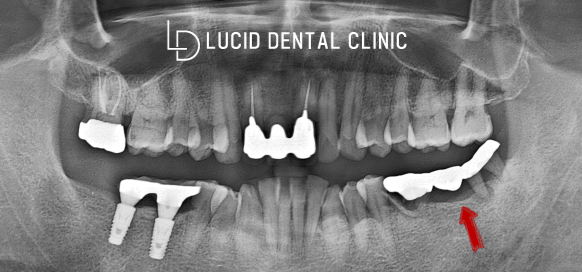

아래 보이는 사진은

초진 파노라마 촬영본으로,

지금까지 수복 받은 치료들이

어떤 것인지 확인할 수 있었는데요

계속해서 불편감을 느낀다고 한 곳은

사진 기준 오른쪽 아래 브릿지입니다.

파노라마를 자세히 살펴보니

브릿지를 지지하고 있는 치아에

치근단 염증이 나타나면서

뿌리 흡수가 진행되고 있었는데요

양옆 지지대가 부실하게 고정되었기 때문에

불편감과 함께 동요를 느끼셨을 것으로 보입니다.